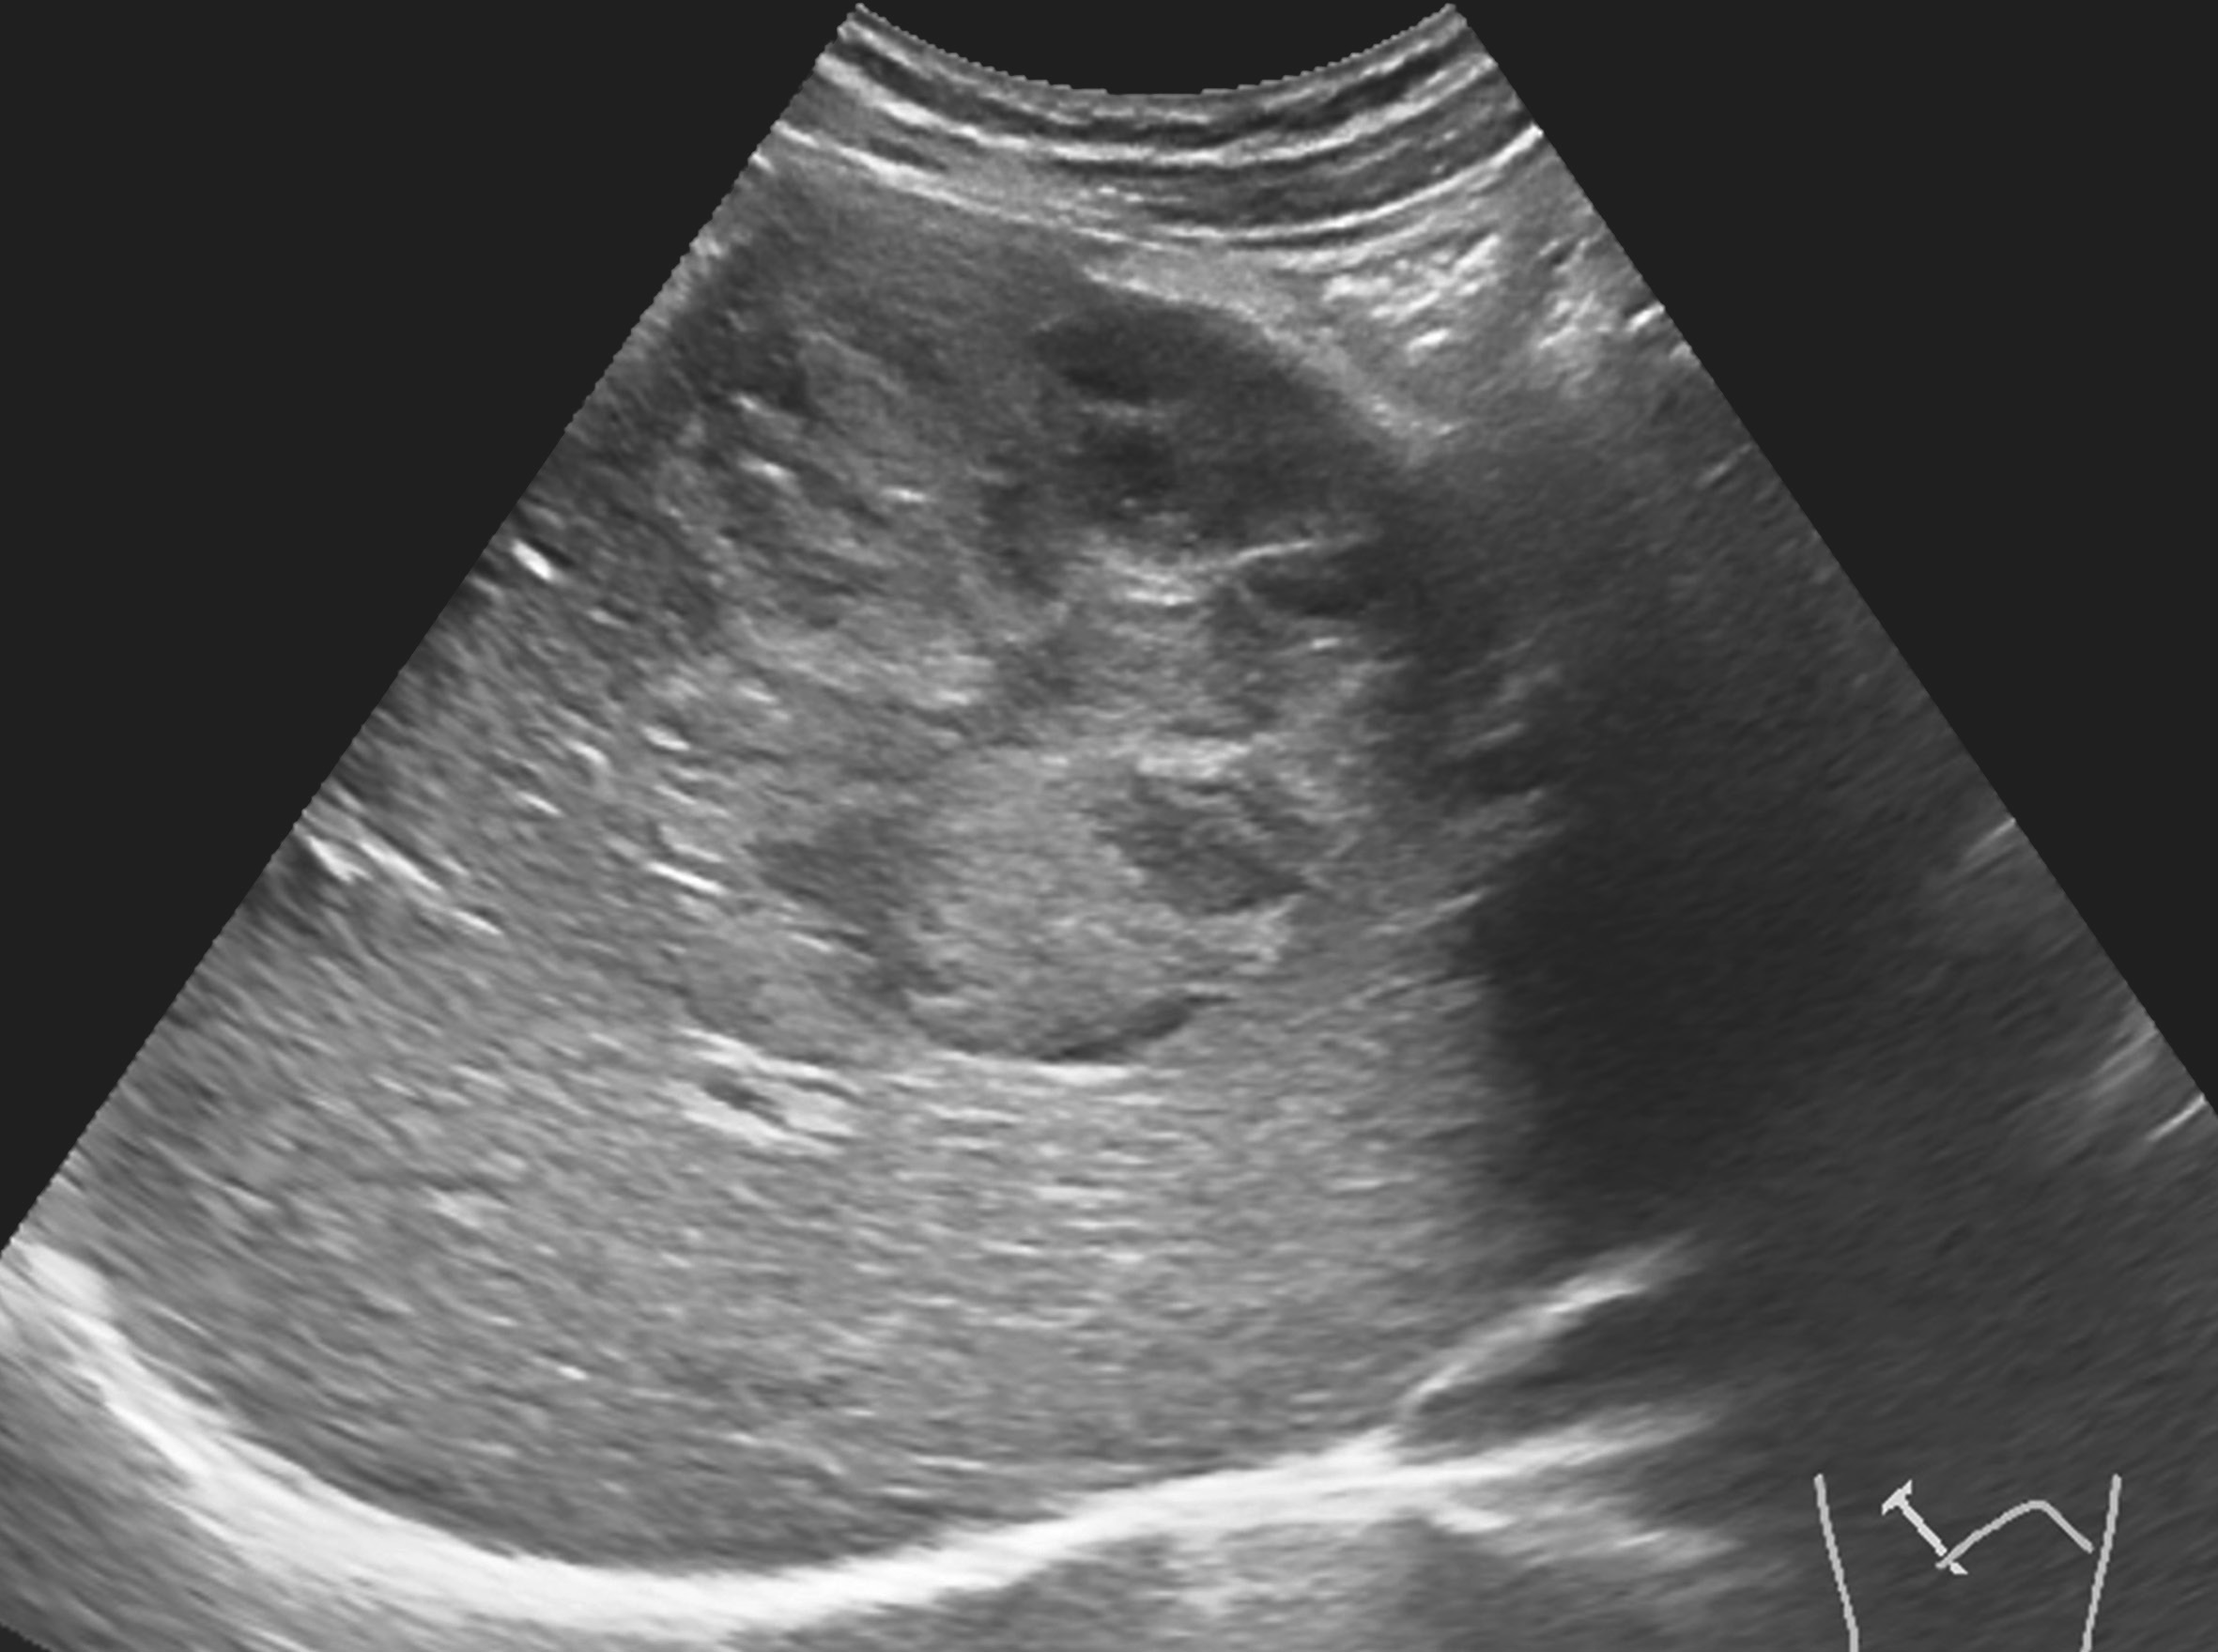

图1-7-2 肝细胞癌CDFI图像

CDFI显示癌结节内部及周边未见明显血流信号